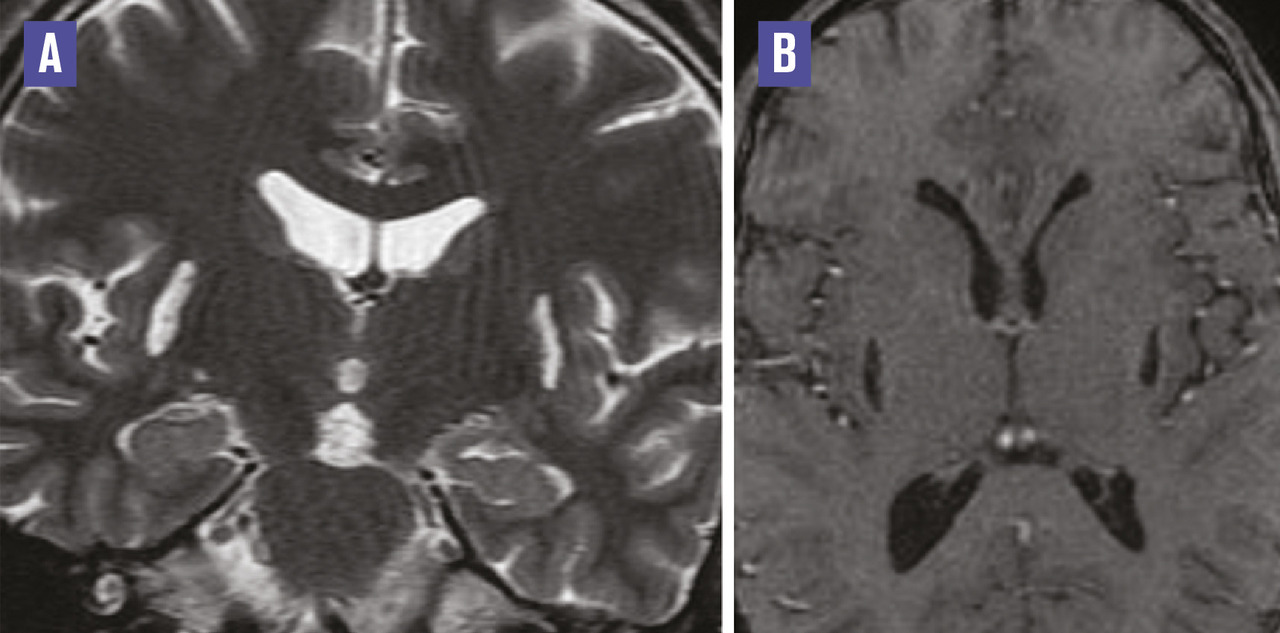

Cet homme de 36 ans, alcoolique chronique, était admis au service d’ophtalmologie pour l’exploration d’une cécité bilatérale. L’imagerie par résonance magnétique (IRM) orbito-encéphalique, demandée dans le cadre du bilan causal, montrait une atteinte putaminale bilatérale et symétrique de signal liquidien ; hyperintense en T2 (fig. 1A ), hypo-intense en T1 et Flair, sans restriction de la diffusion (fig. 2 ) ni rehaussement sur les séquences injectées (fig. 1B ) en rapport avec une nécrose de liquéfaction de type pseudokystique putaminal. Les voies optiques et la substance blanche sous-corticale étaient sans anomalie. Le diagnostic d’une intoxication au méthanol était confirmé par un taux sanguin élevé de méthanol.

L’intoxication au méthanol est une affection sévère dont le pronostic vital et fonctionnel dépend de la rapidité de la prise en charge. De nombreuses intoxications ont été décrites lors de l’utilisation abusive de méthanol dans la fabrication d’alcool frelaté. Le méthanol induit des lésions cytotoxiques d’origine hypoxique par accumulation d’acide formique. Celles-ci prédominent au niveau des noyaux gris centraux, des voies optiques et de certaines régions périphériques sous-corticales de la substance blanche. Leur répartition bilatérale, voire symétrique, est fortement évocatrice. Ces atteintes peuvent toucher aussi le cervelet, l’hypothalamus.1 Au sein des noyaux gris centraux la nécrose putaminale est la lésion la plus fréquemment observée. Ces lésions sont par ailleurs évolutives dans le temps, avec au départ une composante œdémateuse qui laisse ensuite la place à une lésion de nécrose de liquéfaction de type pseudokystique. L’atteinte ophtalmologique survient dans un second temps, avec œdème papillaire, atteinte de la vision des couleurs et baisse de l’acuité visuelle en rapport avec une névrite optique.2